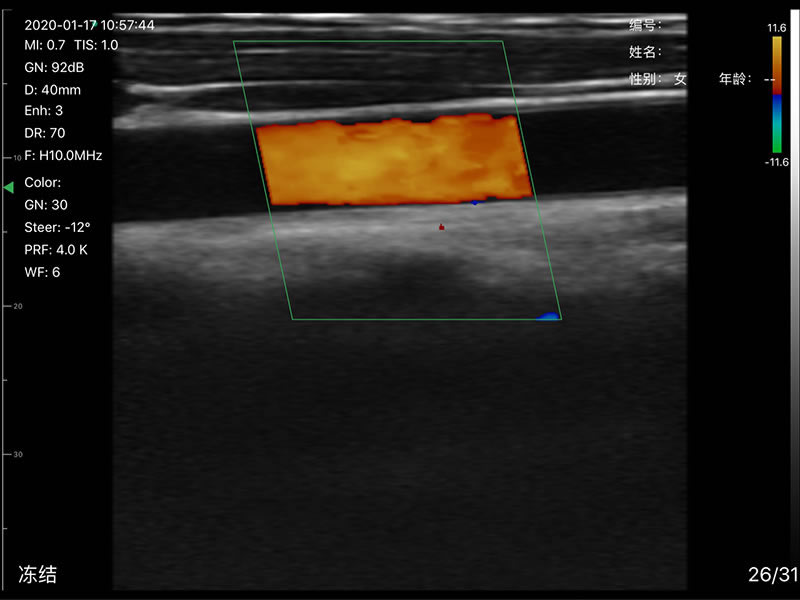

• 探头频率:相控阵2.2/3.6MHz,线阵7.5/10 MHz

• 扫描声头:同时具备微凸、线阵两个声头,并可通过按键快速切换

• 显示模式:B、B/M、Color、PW、PDI